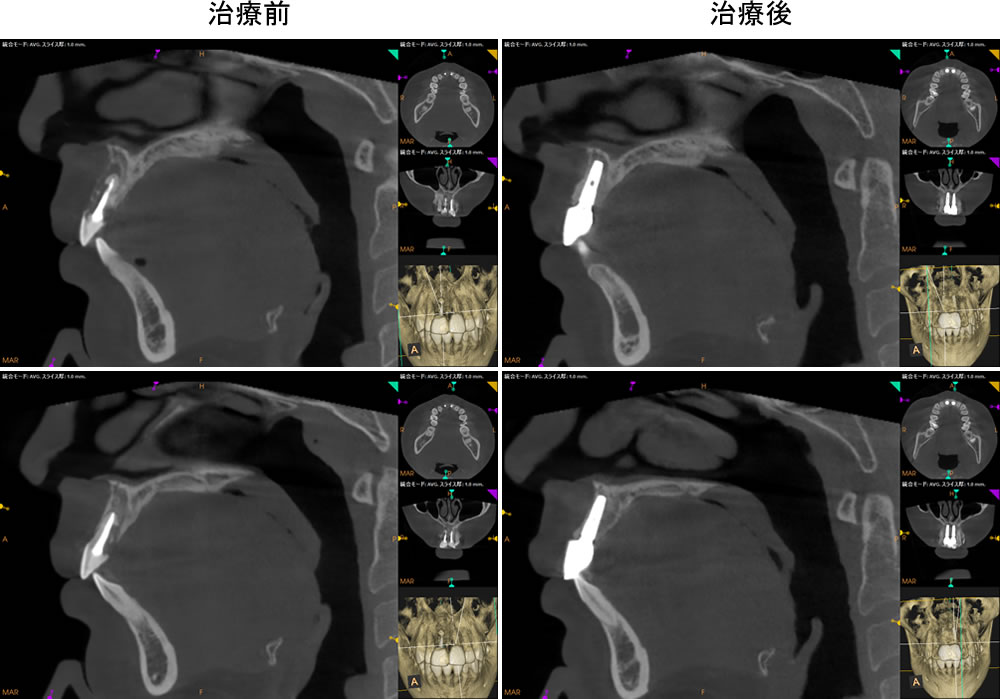

抜歯即時埋入およびPRPを併用した骨造成を行いました。ISQ値(インプラント安定指数)が十分でなかったため、即時荷重(インプラント体を埋入直後、または短期間で仮歯などを装着し、噛む力(咬合力)を加える方法)は行わず、手術を終了しました。

顎骨とインプラントがしっかりと結合したことを確認後、完成した上部構造(人工歯)を装着して治療完了となりました。

治療前後の比較